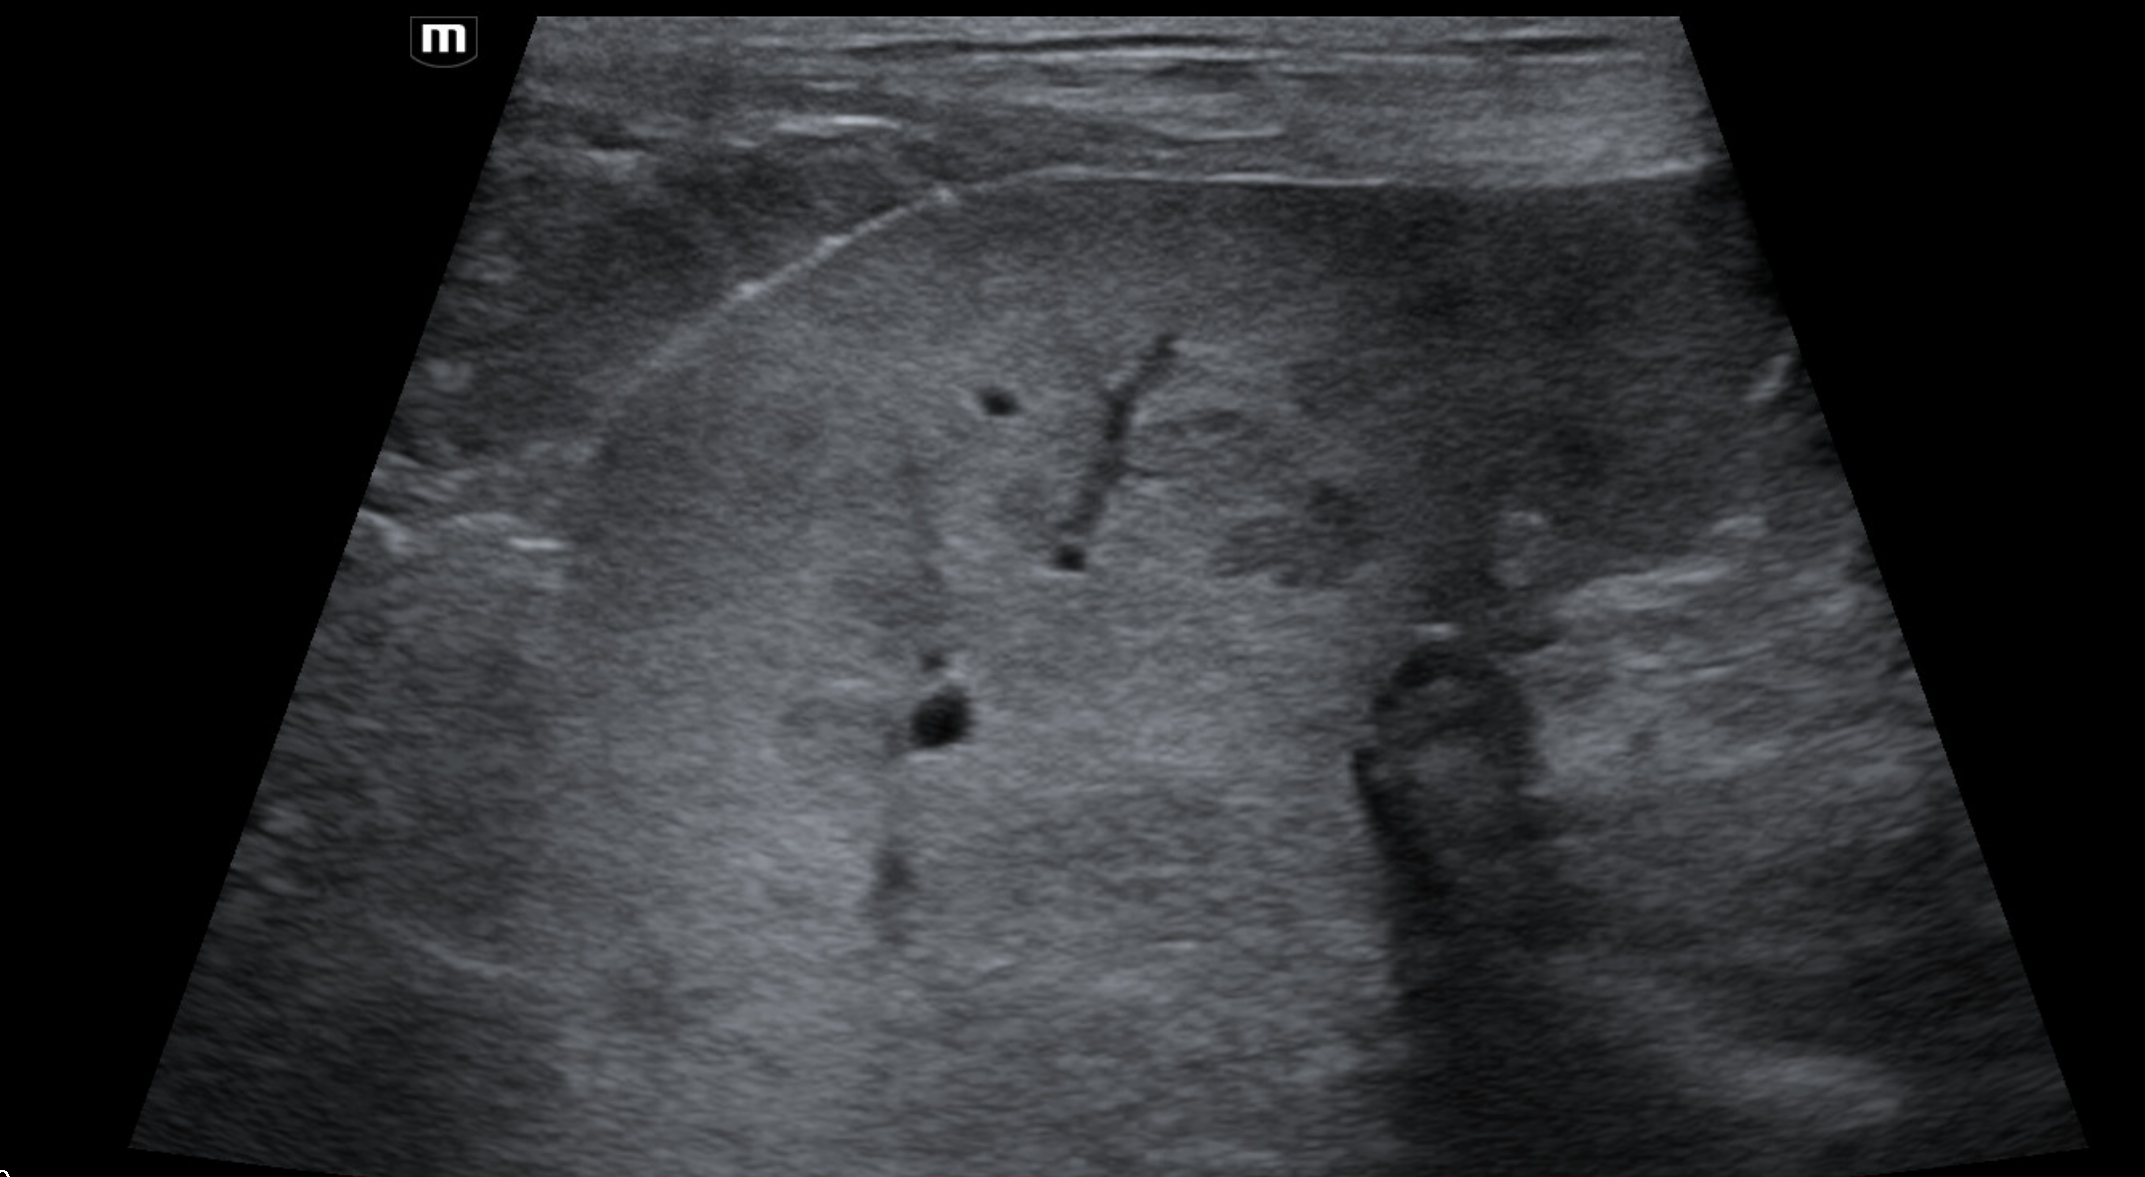

Which of these liver masses/nodules is a malignant tumor.

B-mode ultrasonography is highly sensitive for detecting focal liver lesions but is poorly specific for lesion type. Hepatic masses may appear:

• Hypoechoic, hyperechoic, or mixed echogenicity

• Well-marginated or irregular

• Solitary or multifocal

Importantly, echogenicity does not correlate reliably with malignancy. Multiple studies have demonstrated substantial overlap in the sonographic appearance of benign nodules, primary hepatic tumors, and metastatic lesions (Nyland et al., 2002; O’Brien et al., 2004)

In a large retrospective study of canine liver tumors, no consistent B-mode ultrasonographic features reliably differentiated hepatocellular carcinoma, cholangiocarcinoma, sarcoma, or metastatic lesions, aside from lesion distribution (O’Brien et al., 2004). Hepatocellular carcinomas were more likely to be solitary, whereas sarcomas and metastases were more often multifocal, but significant overlap existed.